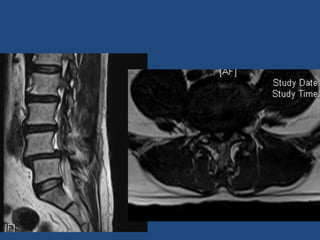

Tb/ Mg – L5 25/M

Tb/ Mg – L5

Tb/ Mg L5